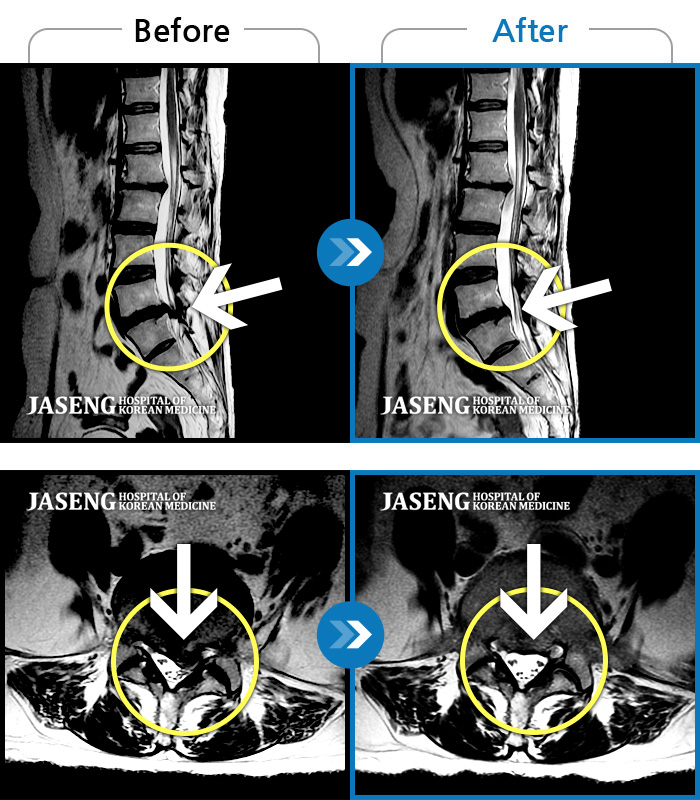

ȯںп Ǹ ǿ ԿǾ, ο ġ ۿ Ƿ ġḦ Ͻñ ٶϴ.